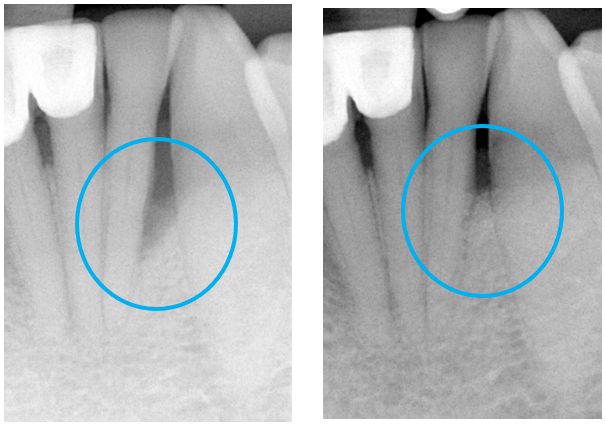

Les chirurgies parodontales à visée régénérative ont pour objectif de restaurer les tissus de soutien perdus à la suite d’une parodontite, en favorisant la reformation du ligament parodontal, de l’os alvéolaire et du cément radiculaire. Ces procédures s’appuient sur des techniques validées scientifiquement, telles que l’utilisation de biomatériaux comme les dérivés de la matrice amélaire (Emdogain) ou l’adjonction de concentrés plaquettaires autologues (PRF/PRP) pour optimiser la cicatrisation.

La sélection de la technique dépend de la morphologie du défaut intra-osseux, de sa profondeur et du nombre de parois résiduelles. Dans les situations favorables, ces interventions permettent une reconstruction mesurable de l’attache parodontale et une amélioration significative du pronostic dentaire.